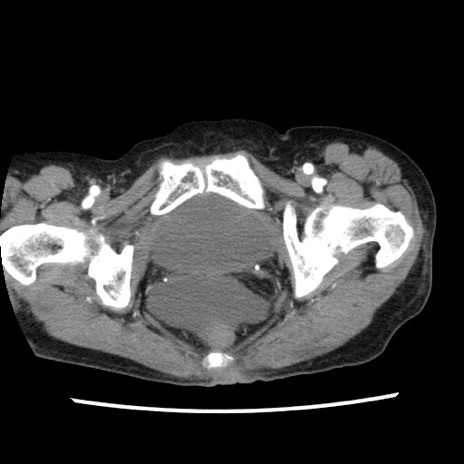

【症例】80歳代女性

【主訴】腹痛

【現病歴】8時間前から腹痛あり来院。

【既往歴】糖尿病、脂質異常症、子宮体癌にて子宮全摘術

【身体所見】意識清明・会話良好だが腹痛で苦悶様、全腹部にわたって反跳痛と圧痛あり

【データ】WBC 13600、CRP 0.14、LDH 224、CK 90